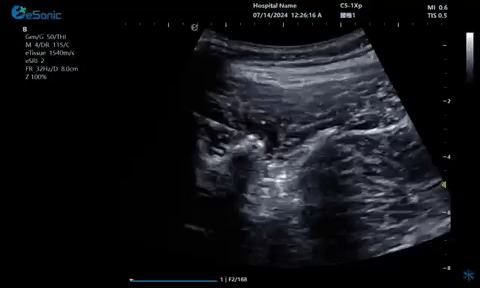

03

超声引导硬膜外麻醉-小等号

管内麻醉

疼痛康复领域中的肌骨超声应用,旨在实现对肌肉、肌腱、韧带、关节、神经、血管、筋膜、滑膜、滑囊、骨膜等组织结构的精确诊断评估。由于超声高频探头对上述机体组织的细微结构具有优异的分辨率,因此能够更为明确地评估这些组织的损伤和炎症状态。同时,超声设备的实时动态评估能力,使得对运动中的相关疾患也能进行准确的评估,这是其他诊断设备所不具备的优势。在康复治疗过程中,肌骨超声还用于介入穿刺治疗,如外周神经阻滞(PNB)、小关节注射、肌筋膜松解术、封闭、小针刀、冲击波治疗等。在超声引导下,这些治疗操作实现了可视化,从而真正意义上实现了精准医疗。以PNB为例,作为一种局部用药方式,其对患者全身干扰小,药物副作用少,且费用较低,因此仍然是临床治疗疼痛的主要方式之一近年来,超声技术在临床康复领域的应用日益凸显其优势。相较于传统的盲穿技术,超声引导下的PNB能够直观显示穿刺和注药过程,无需患者表达异感,避免了反复穿刺给患者带来的痛苦。这种技术显著提高了外周神经阻滞、静脉穿刺的成功率、精确性和安全性,同时减少了不良反应和并发症的发生,为患者带来了福音也相信在不久的将来,eHertz系列产品将会在全球医疗市场上掀起一场技术革新的风暴,让更多的人受益于我国医疗技术的进步。